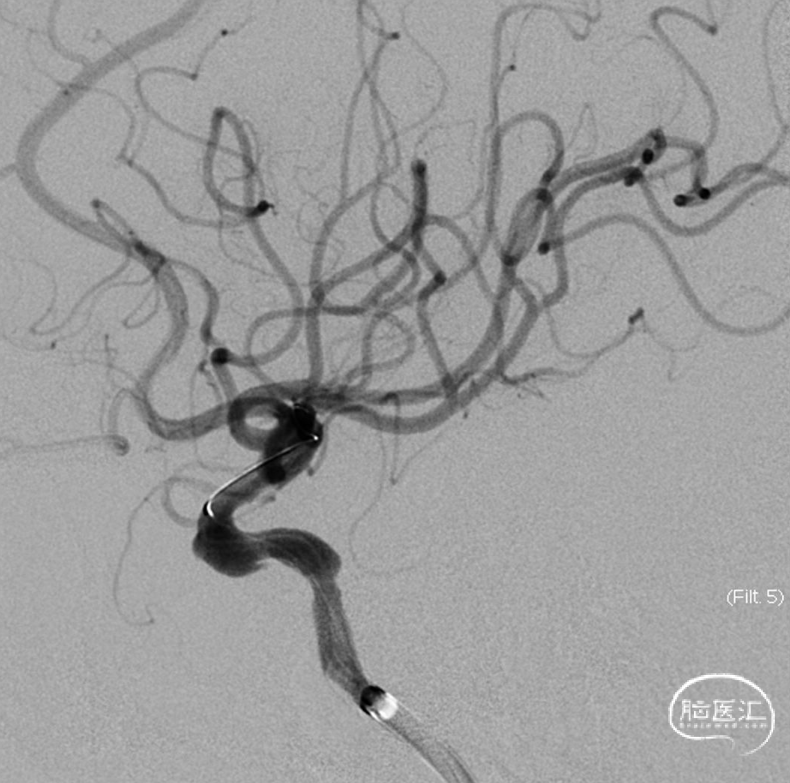

术前影像

右侧颈动脉造影

左侧颈动脉造影

左侧颈内动脉重建(左侧狭窄及扩张较右侧更甚)

手术过程

经Cat5完全释放支架后,拉推送杆后支架近端打开,后将Cat5跟进血流导向装置内尝试“按摩”,支架整体贴壁不够理想。

Cat5通过后海绵窦段狭窄即较前改善

Cat5提供稳定通路,引入3.5mm×10mmHiryu球囊扩张由远端及近端扩张狭窄段及支架贴壁欠佳处

造影示狭窄及贴壁较前进一步改善

导丝成袢,继续“按摩”改善贴壁

“按摩”后再次造影,C2段狭窄仍较明显且贴壁欠佳

再次引入球囊扩张近端

扩张后再次复查造影示支架打开及贴壁较前明显改善

标准正侧位造影未见远端血管栓塞

稀释造影提示支架贴壁可,狭窄改善